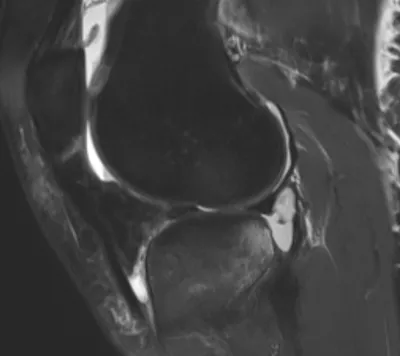

Meniscal Tear Radiology Images

Browse 4 medical images tagged with meniscal tear. This collection includes various imaging modalities for medical education and reference.

- This collection contains 4 radiology images related to meniscal tear, including various imaging modalities such as X-rays, MRIs, CT scans, and ultrasound images commonly used in medical diagnosis and education.